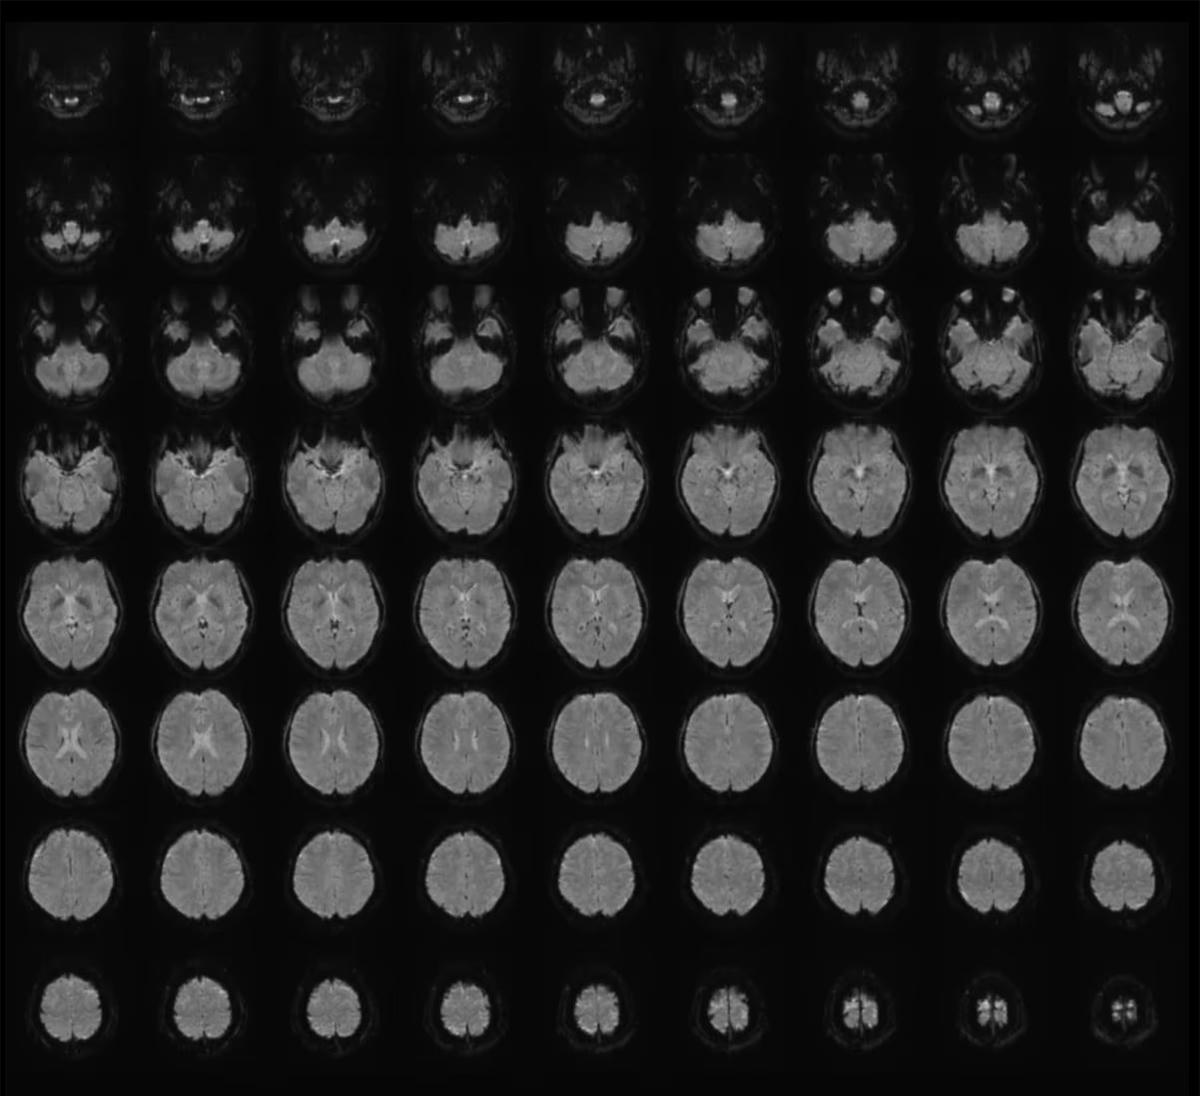

Trong nghiên cứu, Horikawa dùng phương pháp fMRI, chụp cộng hưởng từ chức năng, một kỹ thuật quét não không xâm lấn, để ghi lại hoạt động não của sáu người tham gia trong độ tuổi 22-37. Những người này xem 2.180 đoạn video ngắn không âm thanh, với nội dung đa dạng như vật thể, khung cảnh hay hành động.